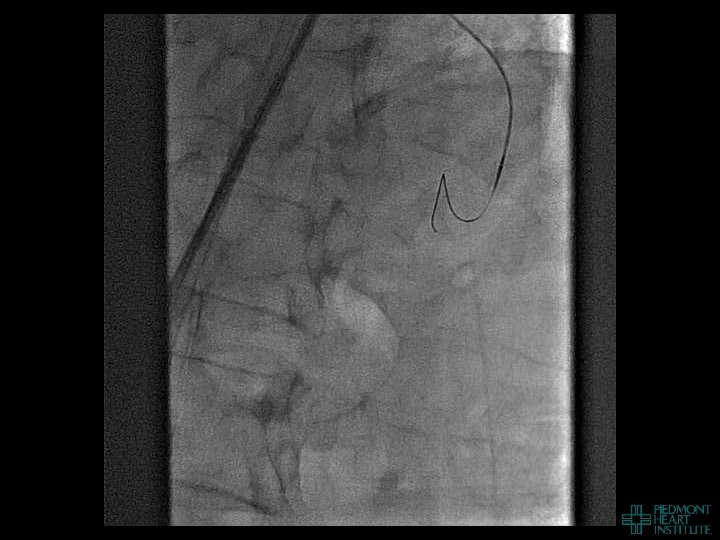

Case Example 2